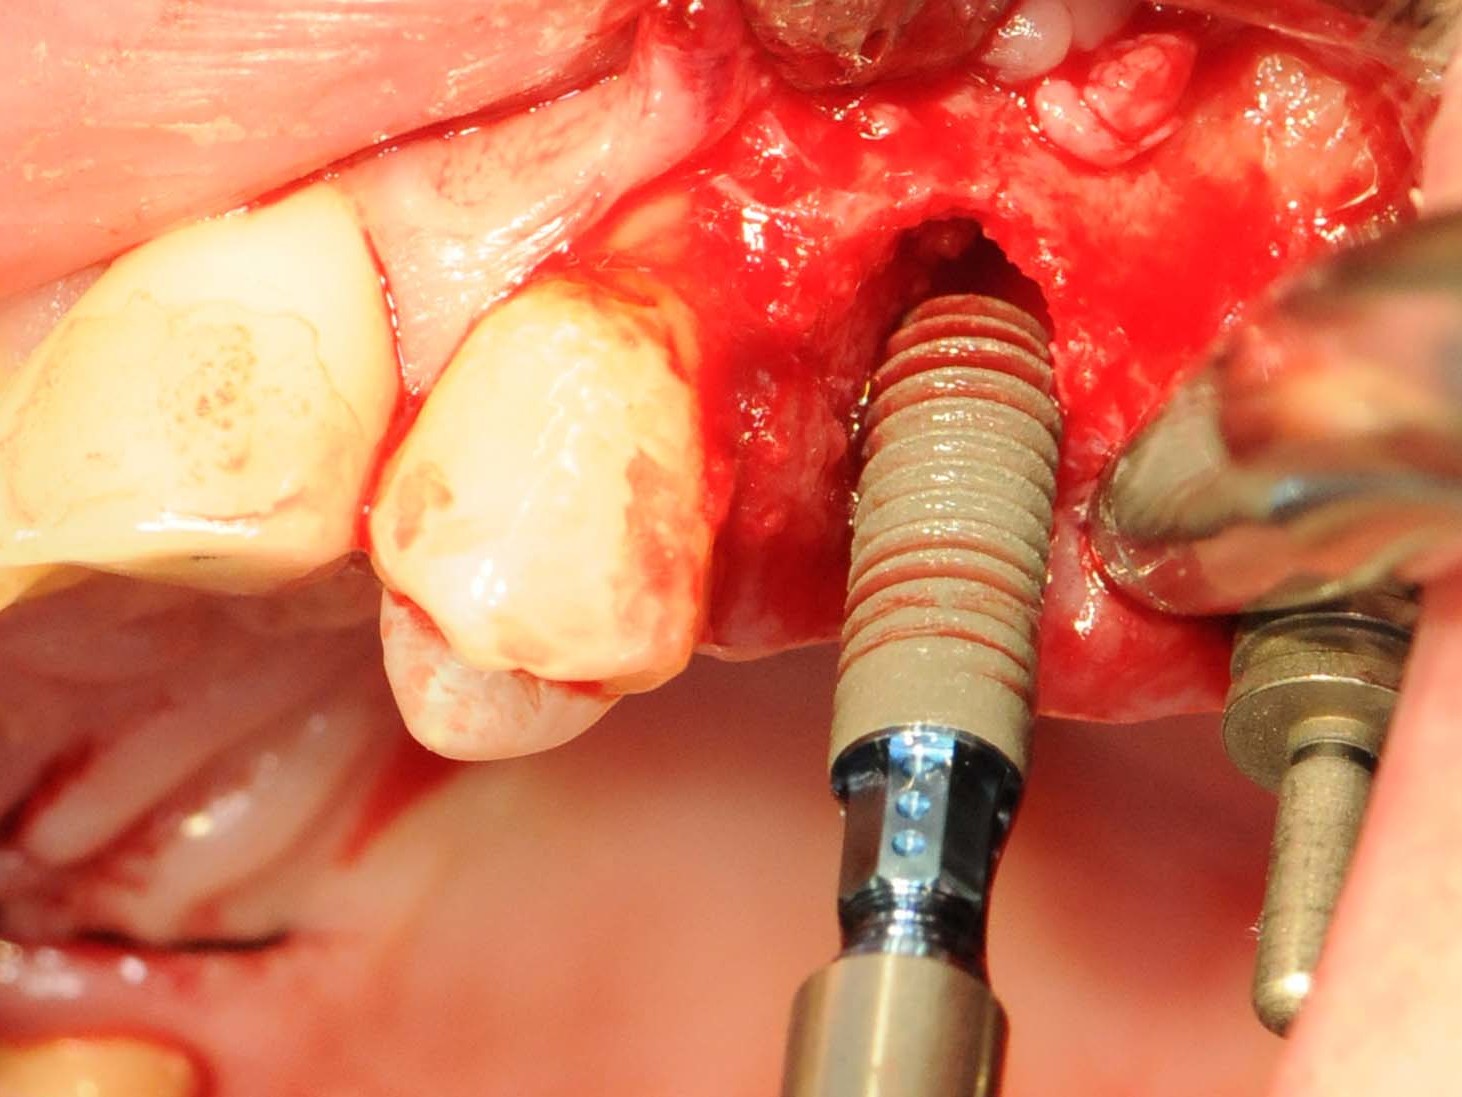

Unter oraler Antibiose mittels Clindamycin 600mg 2 x/Tag erfolgte zunächst die typische minimalinvasive Präparation des Mukoperiostlappens unter Erhalt der Papillen zu den Nachbarzähnen in Regio 12 (Abb. 6), nachdem die Brücke von Zahn 11 nach 14 entfernt wurde (Abb. 7). Wegen Nichtanlage von 13 steht der Zahn 14 in dessen Region. Seinerzeit wurde der Zahn 14 zur Aufnahme einer entsprechenden Eckzahnkrone umgestaltet. Die Implantatbettpräparation (Abb. 8 und 9) für das Straumann PURE Ceramic Implantat (Ø 3,3 mm, Länge 12mm) erfolgte gemäß dem Straumann Guided Surgery Protokoll. Die abschließende Implantatinsertion wurde dem Protokoll für die Straumann PURE Ceramic Implantatlinie gemäß durchgeführt (Abb. 10 und 11). In der Implantatsetzungsregion des zweiten Quadranten wurde zunächst die Inlay-Brücke von Zahn 25 nach 27 entfernt. Seitens des zahntechnischen Labors wurde das Zahninlay von Zahn 27 von der Brücke getrennt und wieder inkorporiert. Nach der Extraktion des tief zerstörten Zahnes 25 erfolgte die typische Mukoperiostlappenpräparation. Nach Darstellung des Insertionssitus kam die massive vestibuläre Knochendefizitsituation in Regio 26 zur Darstellung (Abb. 12). Zunächst wurde die Präparation der Implantatstollen in Regio 25 und 26 gemäß dem Straumann Guided Surgery-Protokoll durchgeführt. In Regio 25 wurde ein Straumann Bone Level Roxolid Implantat (Ø 4,1 mm, Länge 12mm) als Sofortimplantation eingesetzt (Abb. 13 und 14). In Regio 26 wurde ein Knochenring CHB¹⁶ zur Augmentation des vestibulären Knochendefizits entsprechend des ossären Knochenabhanges angeschrägt und in der Höhe eingekürzt (Abb. 15). Die Anpassung des homologen Ringes erfolgt unter Fixierung mit der bonering fix-Zange und Anwendung einer 10-mm-Diamanttrennscheibe (Abb. 16).

Bohrung über Guided Surgery

Abb. 8: Bohrung über Guided Surgery

Abb 9 Überprüfung der Implantatachse nach der Pilotbohrung

Abb. 9: Überprüfung der Implantatachse nach der Pilotbohrung

Abb 10 Einbringen des Straumann® PURE Ceramic Implantat

Abb. 10: Einbringen des Straumann® PURE Ceramic Implantat

Abb 11 Straumann® PURE Ceramic Implantat in situ

Abb. 11: Straumann® PURE Ceramic Implantat in situ